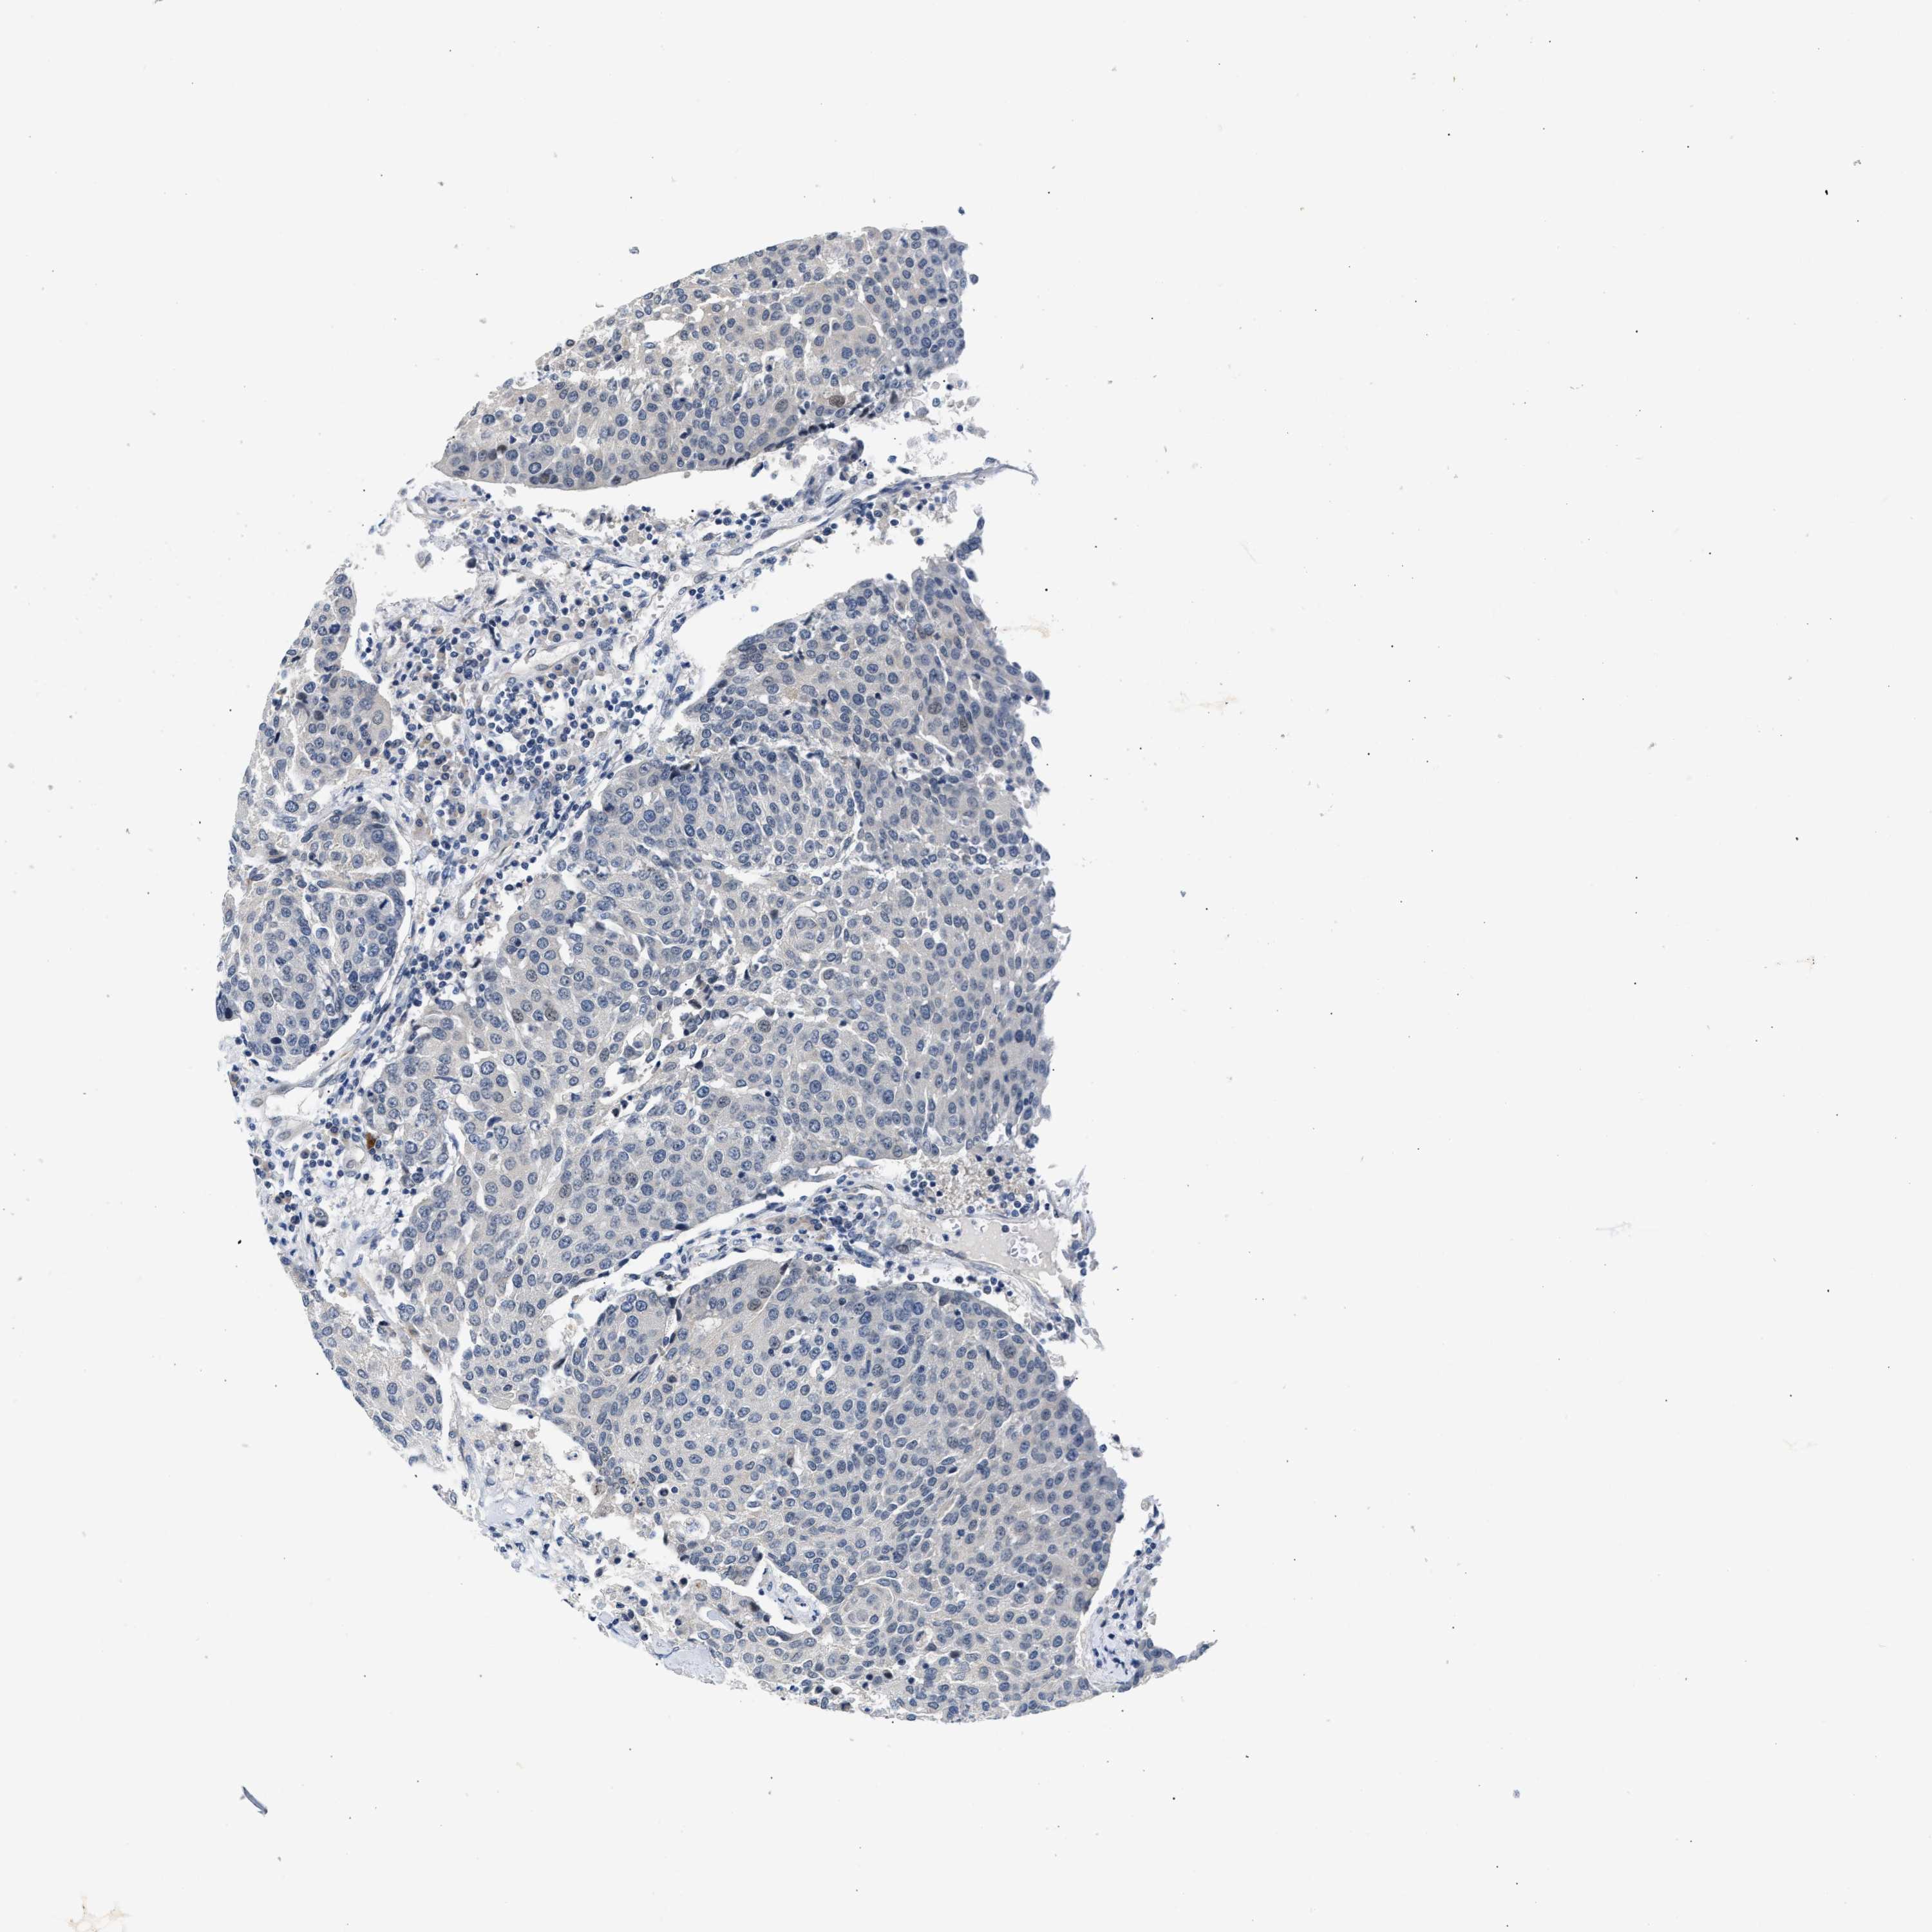

UROTHELIAL CANCER - Protein expressioni

A mouse-over function shows sample information and annotation data. Click on an image to view it in a full screen mode. Samples can be filtered based on level of antibody staining by selecting one or several of the following categories: high, medium, low and not detected. The assay and annotation is described here.

Note that samples used for immunohistochemistry by the Human Protein Atlas do not correspond to samples in the TCGA dataset.

Antibody stainingi

Antibody staining in the annotated cell types in the current human tissue is reported as not detected, low, medium, or high, based on conventional immunohistochemistry profiling in selected tissues. This score is based on the combination of the staining intensity and fraction of stained cells.

Each image is clickable and will lead to virtual microscopy that enables deeper exploration of all samples and also displays staining intensity scores, fraction scores and subcellular localization as well as patient and tissue information for each sample.

Antibody HPA044244

Antibody HPA058777

Antibody CAB020694

Staining

High

Medium

Low

Not detected

Intensity

Strong

Moderate

Weak

Negative

Quantity

>75%

75%-25%

<25%

None

Location

Nuclear

Cytoplasmic/membranous

Cytoplasmic/membranous,nuclear

Urothelial carcinoma, High grade

Urothelial carcinoma, Low grade

Urothelial carcinoma, NOS